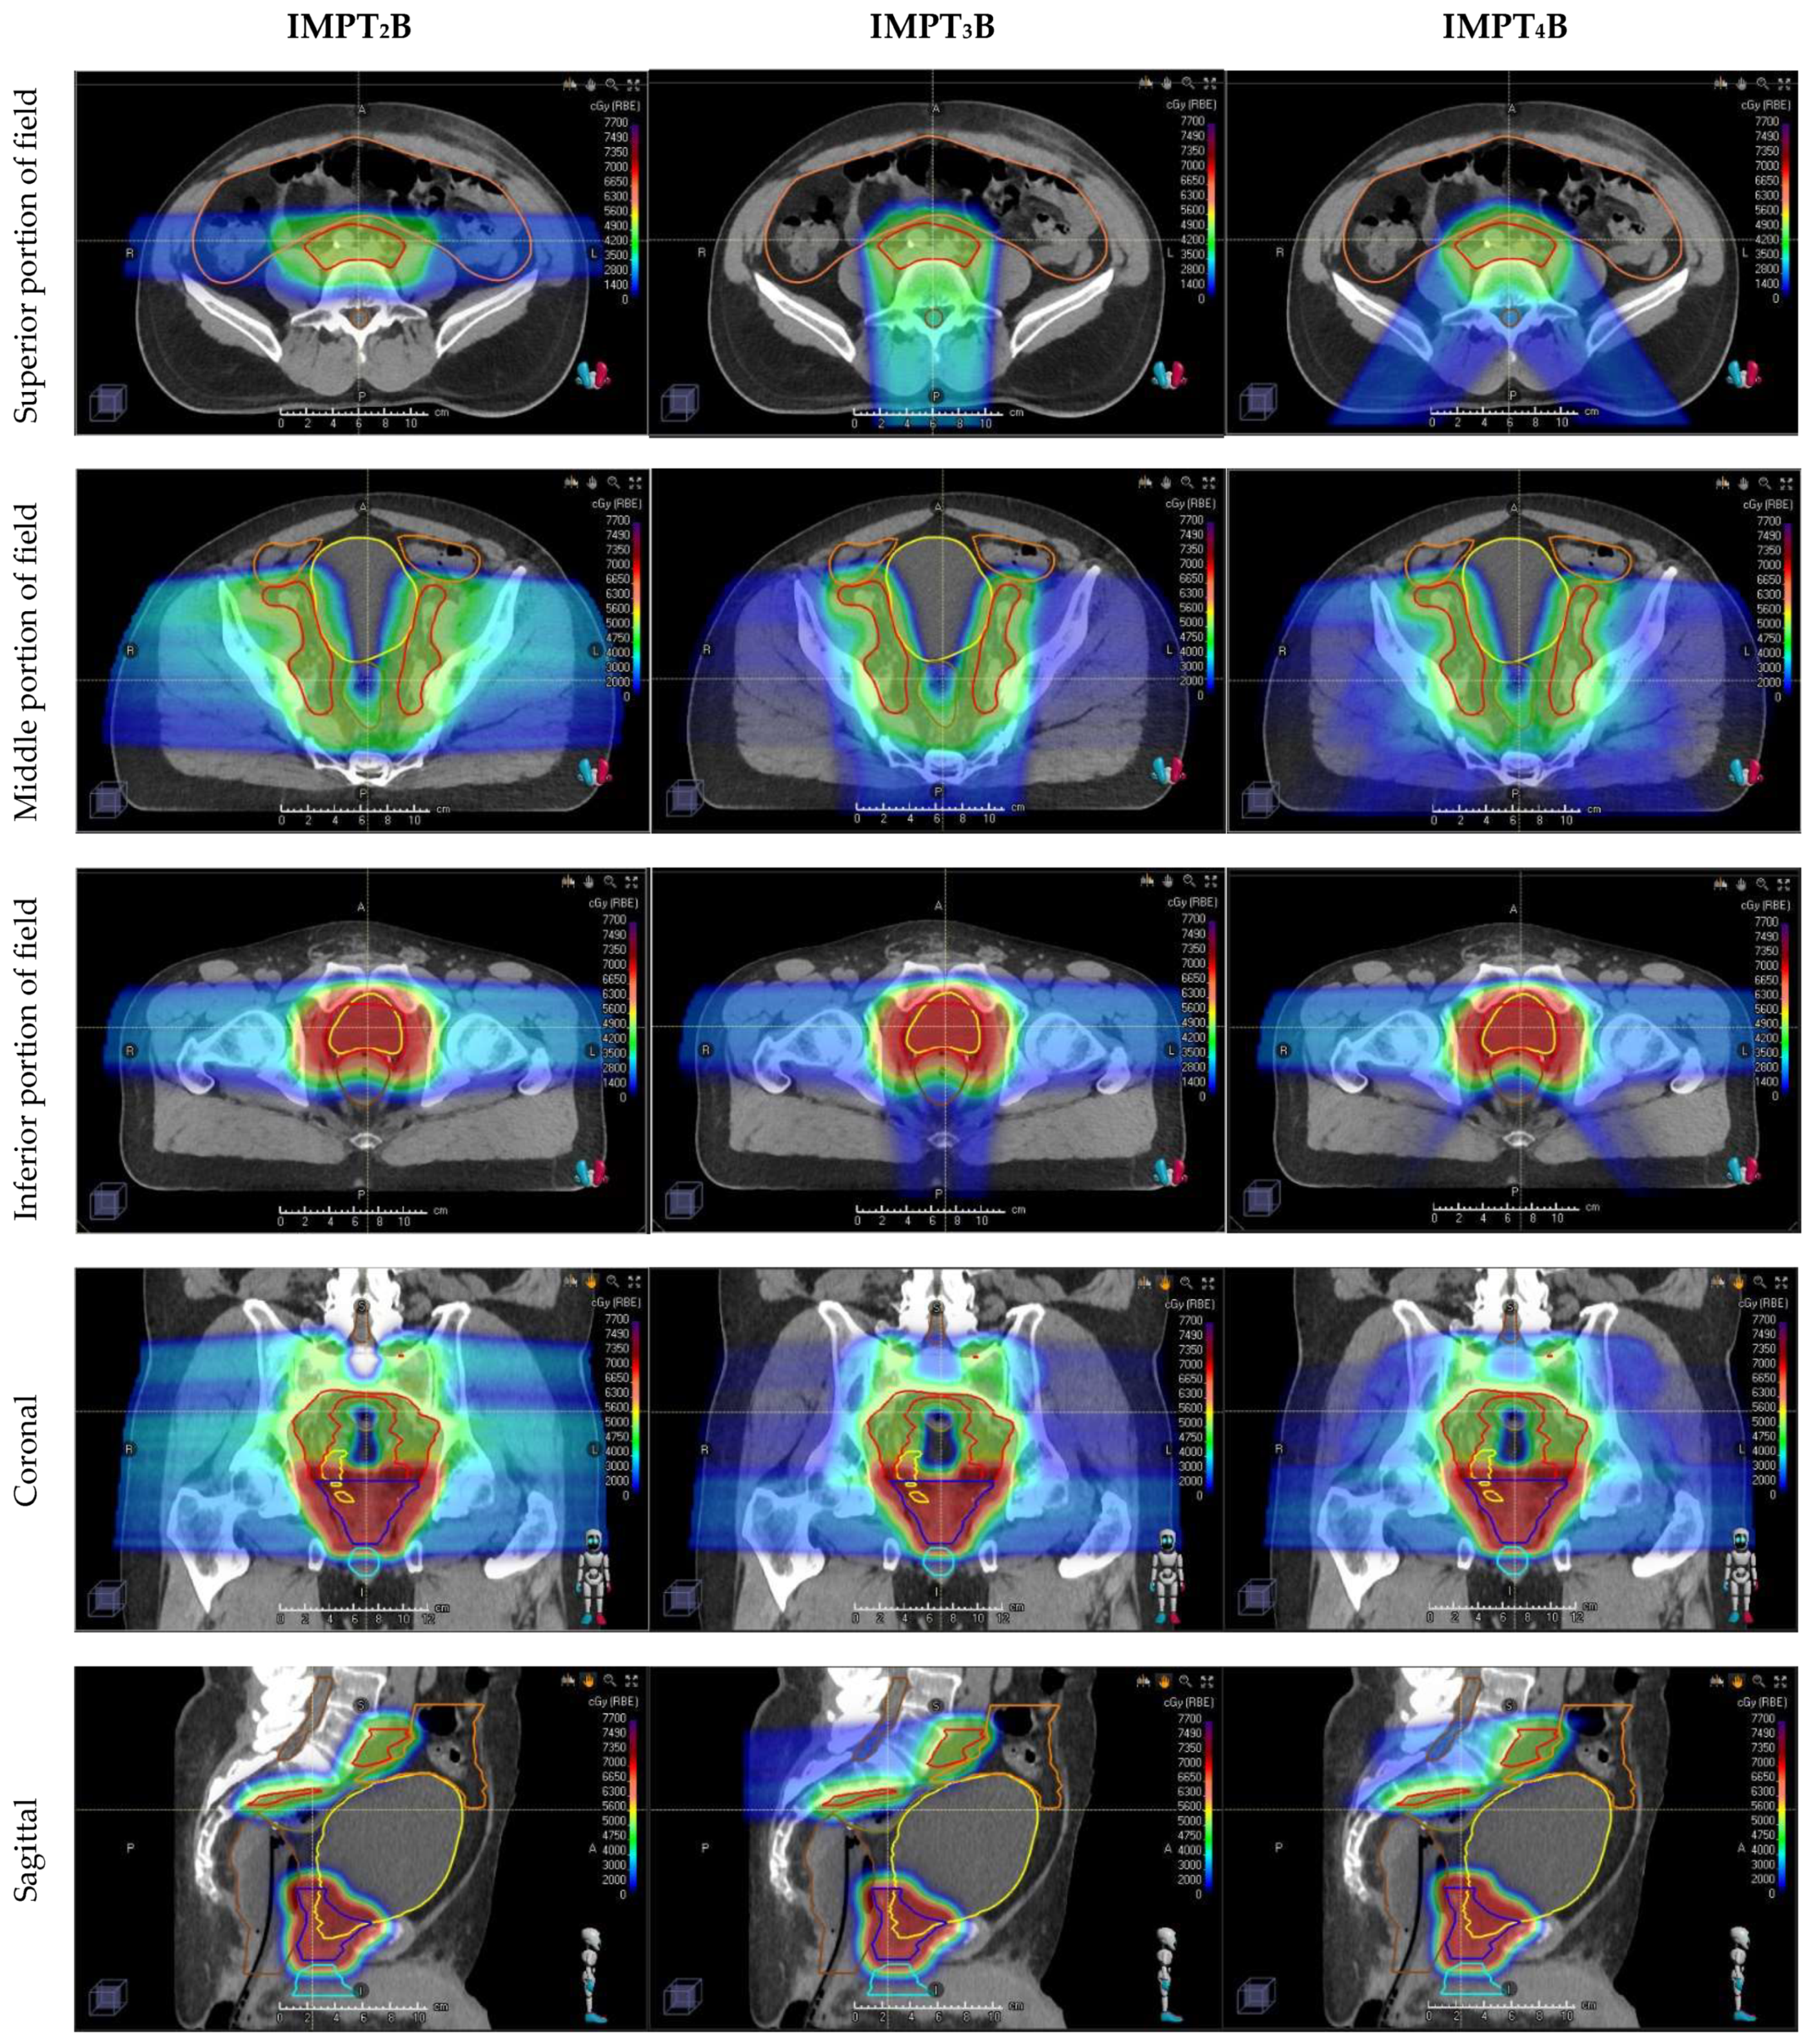

| IMPT2B | two-field IMPT beam arrangement using opposed laterals |

| IMPT3B | three-field IMPT beam arrangement using opposed laterals inferiorly matched to a Posterior–anterior beam superiorly |

| IMPT4B | four-field IMPT beam arrangement using opposed laterals inferiorly matched to 2 Posterior oblique beams superiorly |

4.1. Beam Arrangements